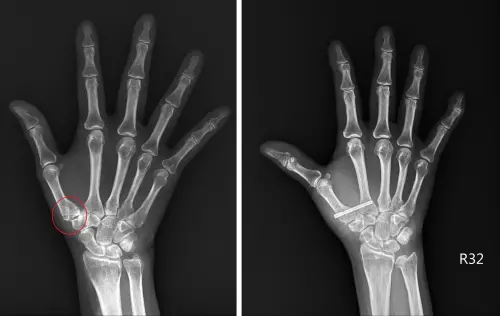

▲患者術前X光可發現拇指根部關節有滑脫情形(左),新型微創手術用鈦合金或可吸收螺絲將其固定在第二掌骨基部(右),順利改善症狀。(圖/台北慈院提供) 周博智說明,此病變經X光檢查可判斷關節磨損程度,若程度尚輕,用貼紮或護腕固定,加上止痛藥物即可控制,嚴重病例則需手術處理,而目前主流術式是開一個6~8公分的傷口再將磨損關節切除,但切除後關節呈中空容易晃動,所以會取一條手腕的肌腱,將其部分剖半後,塑成球狀再放入切除的空間當作「地基」。

周博智指出,為減少疼痛並兼顧靈活度與握力,可採新式微創手術,先在手腕開0.5~1公分的入口,再將滑脫關節矯正至關節軸心,並將可吸收的螺釘固定於第二掌骨基部,即可分攤拇指基部的受力,也不會犧牲拇指的靈活度,且這項治療能在當日完成,病人免住院,,一週後拆線後即可開始練習手部活動度及力量。